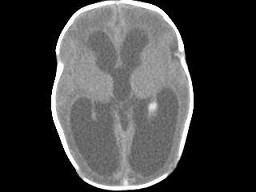

问题 1岁,女,头颅呈球状,颅骨透光试验阳性,请结合CT图片,选择最可能的诊断 ( )

选项 A、先天性脑积水 B、重度脑积水 C、慢性双侧性巨大硬膜下血肿 D、水瘤 E、脑严重缺血

答案 A